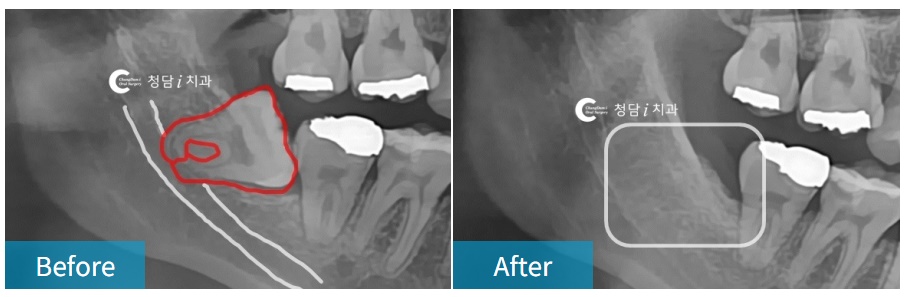

매복 사랑니, 신경과 가깝거나 엑스레이에 중첩되어 보이는 사랑니,

뿌리가 휘어있는 사랑니, 거꾸로 누워있는 사랑니 등

“턱 신경과 가까이 있는 오래된 매복 사랑니 발치했어요.

치조골의 구조, 신경관 위치, 치아의 각도 등을 정확히 파악하고,

주변의 뼈 손상을 최소화하며 빠르게 뽑아야 환자의 고통을 줄일 수 있기 때문에

내원하시면 X-ray와 CT 촬영 후 신경과의 거리, 뿌리의 방향 등을 분석한 후 발치를 진행하게 됩니다.